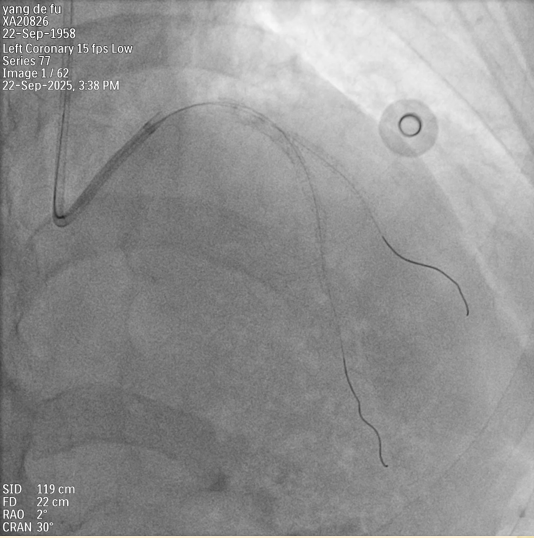

在冠心病诊治方面,我们结合中医辨证与西医评估,综合运用心脏核磁共振、多模态冠脉影像与功能学检查(如FFR、IVUS、OCT),精准评估冠脉病变性质与心肌缺血程度,为患者制定个体化治疗方案。在此基础上,我们发挥中医药在胸痹心痛二级预防中的特色优势,形成了一系列疗效确切的中西医结合综合干预方案。